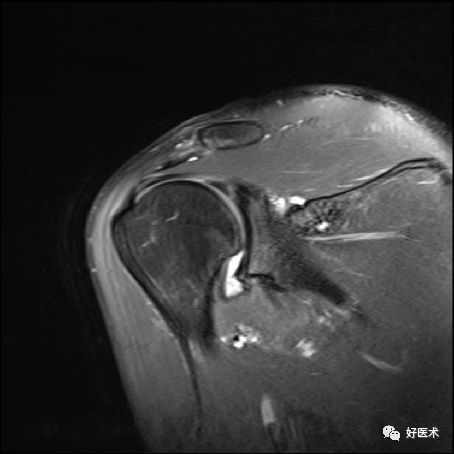

冈上肌完全撕裂

冈上肌全层撕裂伴肩撞(骨赘形成)

冈上肌全层撕裂MRI间接关节造影表现

冈上下肌撕裂